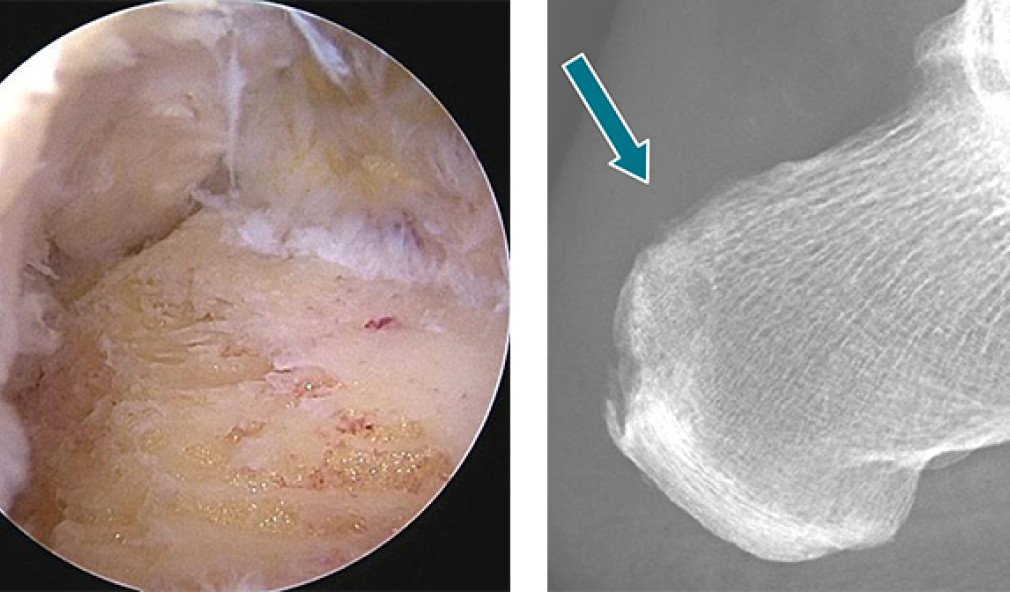

MRI-Bild Fuss mit belastungsinduziertem Logensyndrom

Belastungsinduziertes Logensyndrom des Grosszehen-Spreizer-Muskels

Ein Patient suchte uns wegen starker Schmerzen an der linken Fusssohle beim Joggen auf. Ursache war ein Logensyndrom, auch Kompartmentsyndrom genannt, des Grosszehenspreizer-Muskels. Erfahren Sie im  Fallbeispiel, wie wir zur Diagnose kamen und wie wir dem Patienten mit einer Operation helfen konnten.